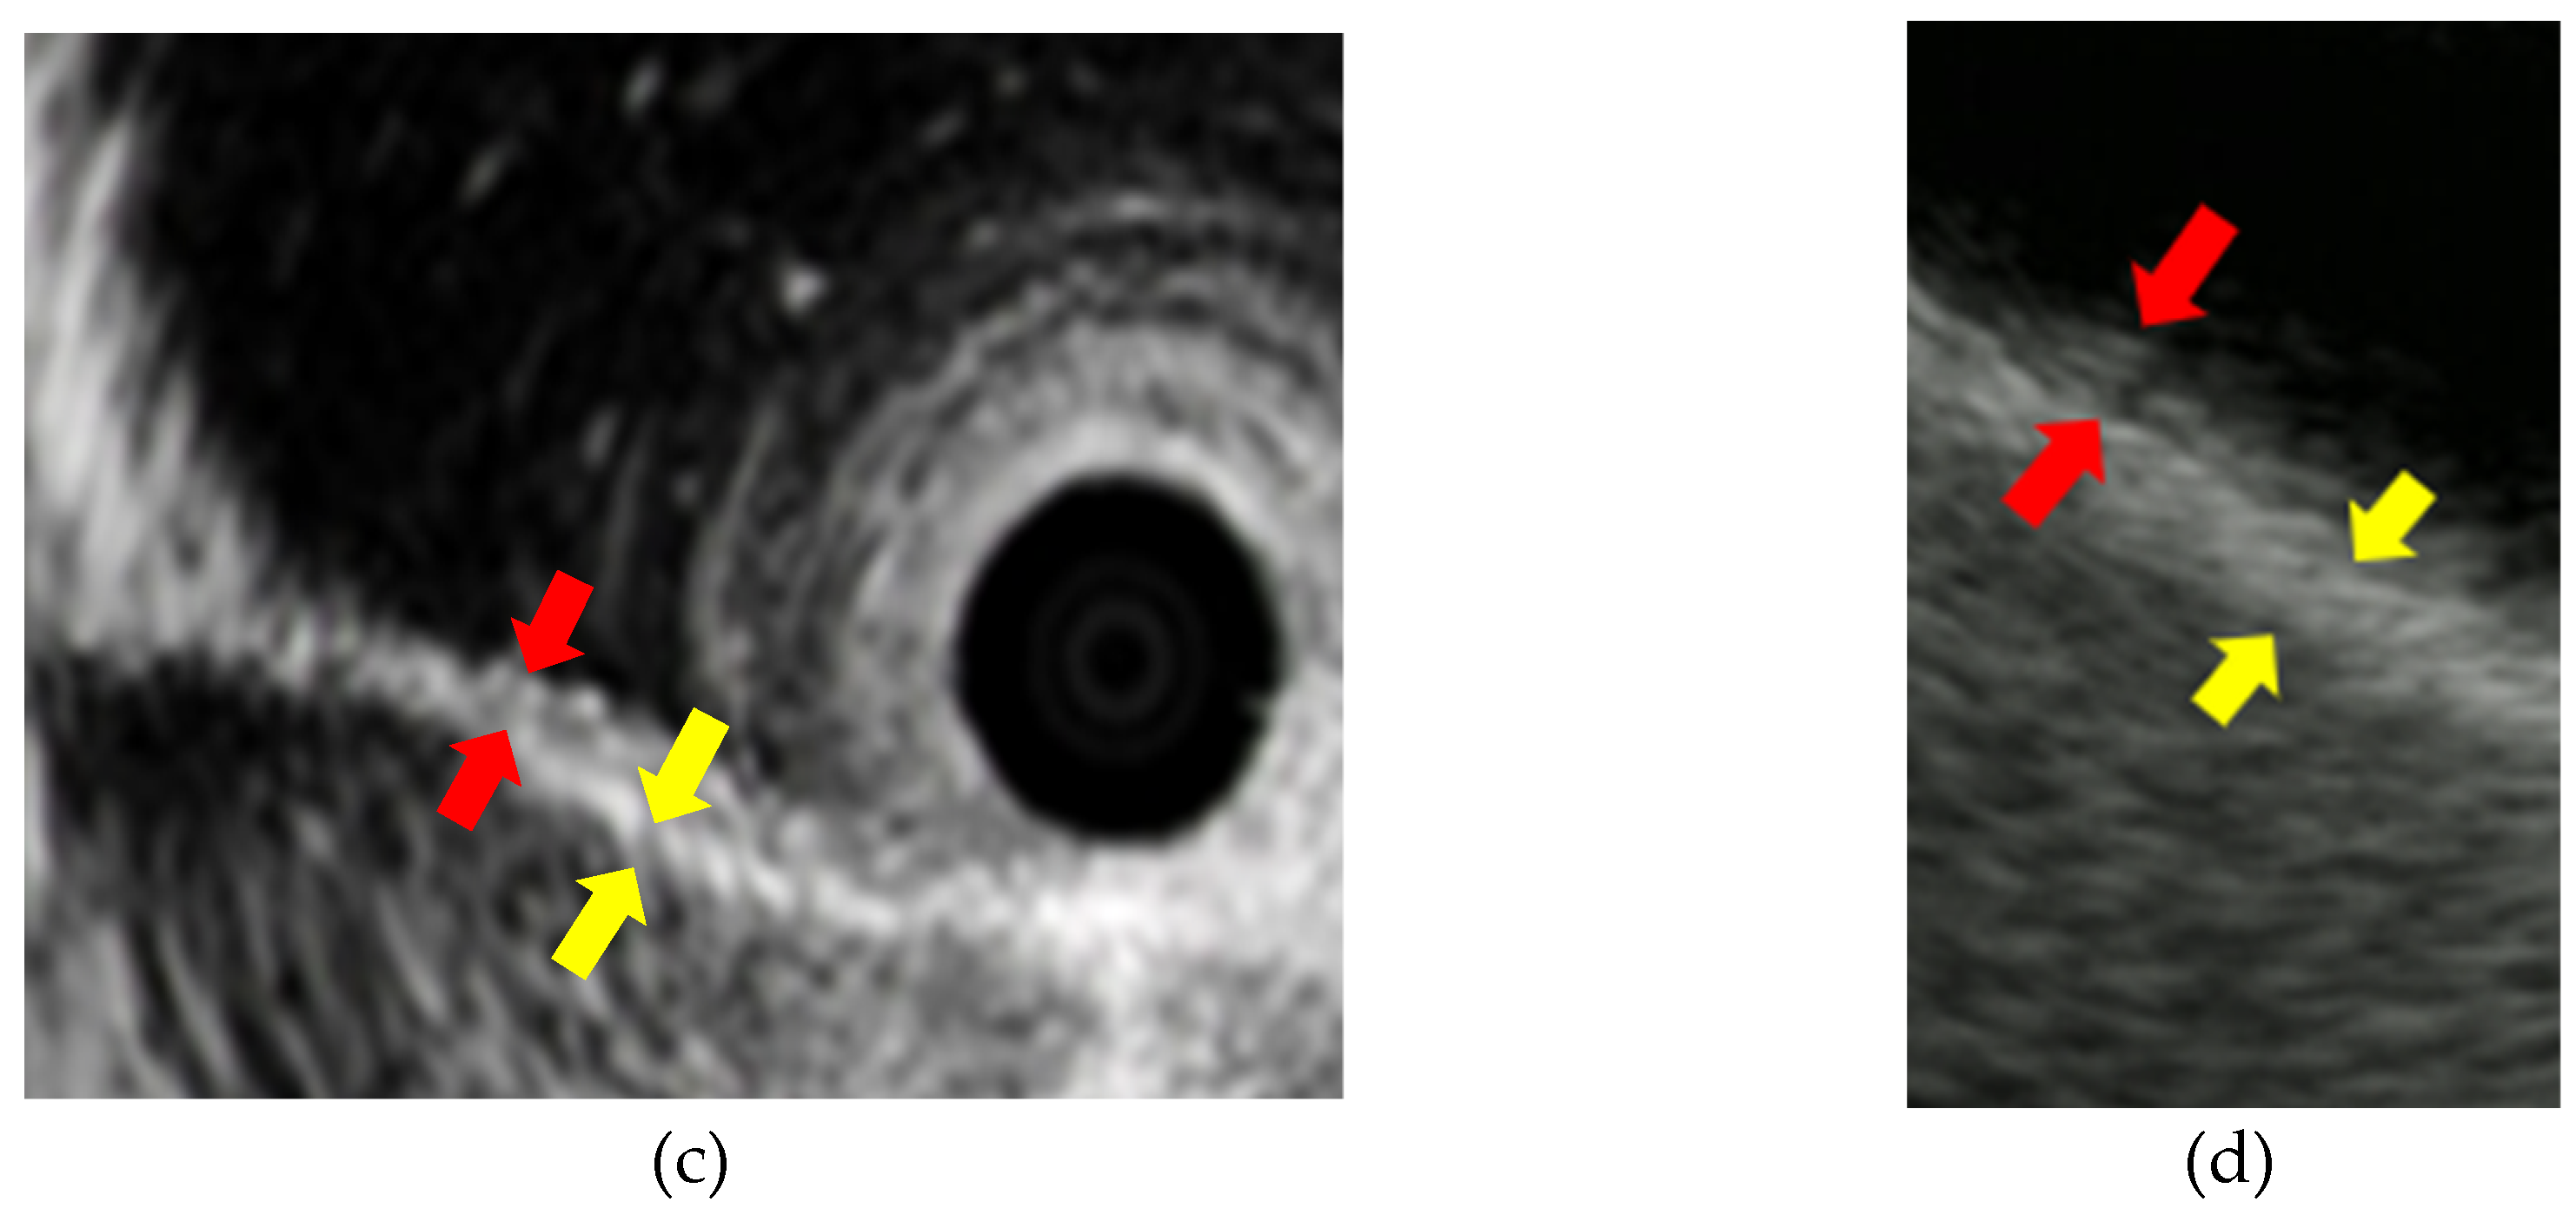

Choledocholithiasis is the most common benign biliary disease encountered in clinical practice, and can sometimes be complicated by severe acute cholangitis, which requires biliary drainage. Diagnostic modalities for choledocholithiasis include abdominal ultrasound (AUS), computed tomography (CT), magnetic resonance cholangiopancreatography (MRCP), and EUS. In some cases, IDUS may also be employed. The sensitivity for detecting choledocholithiasis is 63% for AUS, 71% for CT, and 96% for EUS [10]. AUS and CT tend to show particularly poor diagnostic ability for choledocholithiasis in patients with small stones or stones in a non-dilated common bile duct. The specificity of EUS for detecting choledocholithiasis is near to 100%, and is higher than that of AUS (95%) and CT (97%) [10]. MRCP is also an effective modality for the diagnosis of choledocholithiasis; a meta-analysis found sensitivity and specificity for diagnosing choledocholithiasis of 96% and 92%, respectively, for EUS, and 85% and 90% for MRCP [11]. Suzuki et al. [12] also reported that EUS had superior diagnostic ability to MRCP for choledocholithiasis that was missed on CT, with the high spatial resolution of EUS making it the most reliable and efficient diagnostic modality for small lesions [13,14,15,16,17] [Figure 3].

Figure 3. Detection of small choledocholithiasis by intraductal ultrasound (IDUS) and endoscopic ultrasound (EUS): (a) IDUS image of choledocholithiasis (arrow, 5 mm); (b) EUS image of choledocholithiasis (arrow head, 5 mm).